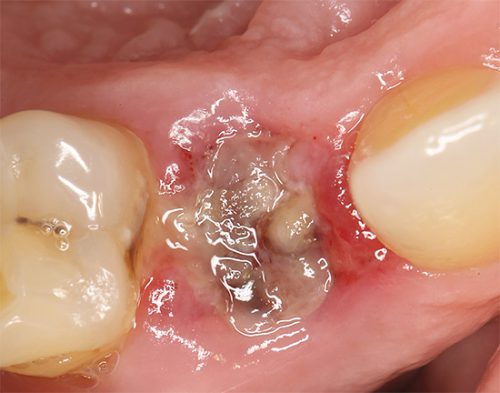

- Сухая лунка. В полости нет сгустка крови, с которого начинается заживание. Причиной осложнения могут быть нарушения процесса тромбообразования, прием препаратов, уменьшающих свертывание (кардиоаспирин), слишком интенсивное полоскание рта. Сухая лунка может стать причиной проникновения болезнетворных бактерий, длительного заживления ранки.Как лечить нарушение, скажет лечащий врач.

Часто причиной альвеолита является травматичность стоматологической процедуры. Травма может быть получена , если зуб удаляли,по фрагментам (частям). В процессе операции иногда повреждается десна или частично разрушаются костные стенки лунки. В этом случае заживление происходит более длительно по сравнению с неосложненным удалением и нередко сопровождается появлением альвеолита.

Попадание в лунку инородных частиц

Иногда боли после удаления зуба возникают в результате попадания в лунку содержимого кариозной полости, зубных отложений, осколков удаленного зуба или костных фрагментов альвеолы. Кроме этого, причиной болей и альвеолита может стать разрушение кровяного сгустка.

Несоблюдение гигиены лунки

Заживление альвеолы происходит благодаря образованию кровяного сгустка. Этот биологический барьер защищает лунку от попадания инфекций и воспаления. Через некоторое время сгусток замещается вновь образовавшейся костной тканью. Не рекомендуется в течение суток после стоматологической процедуры употреблять грубую, горячую или острую пищу, так как это может разрушить кровяной сгусток. Кроме этого, чистить зубы и полоскать рот необходимо с осторожностью. Несоблюдение рекомендаций стоматолога может привести к нарушению кровяного сгустка, появлению альвеолита и болей после удаления зуба.